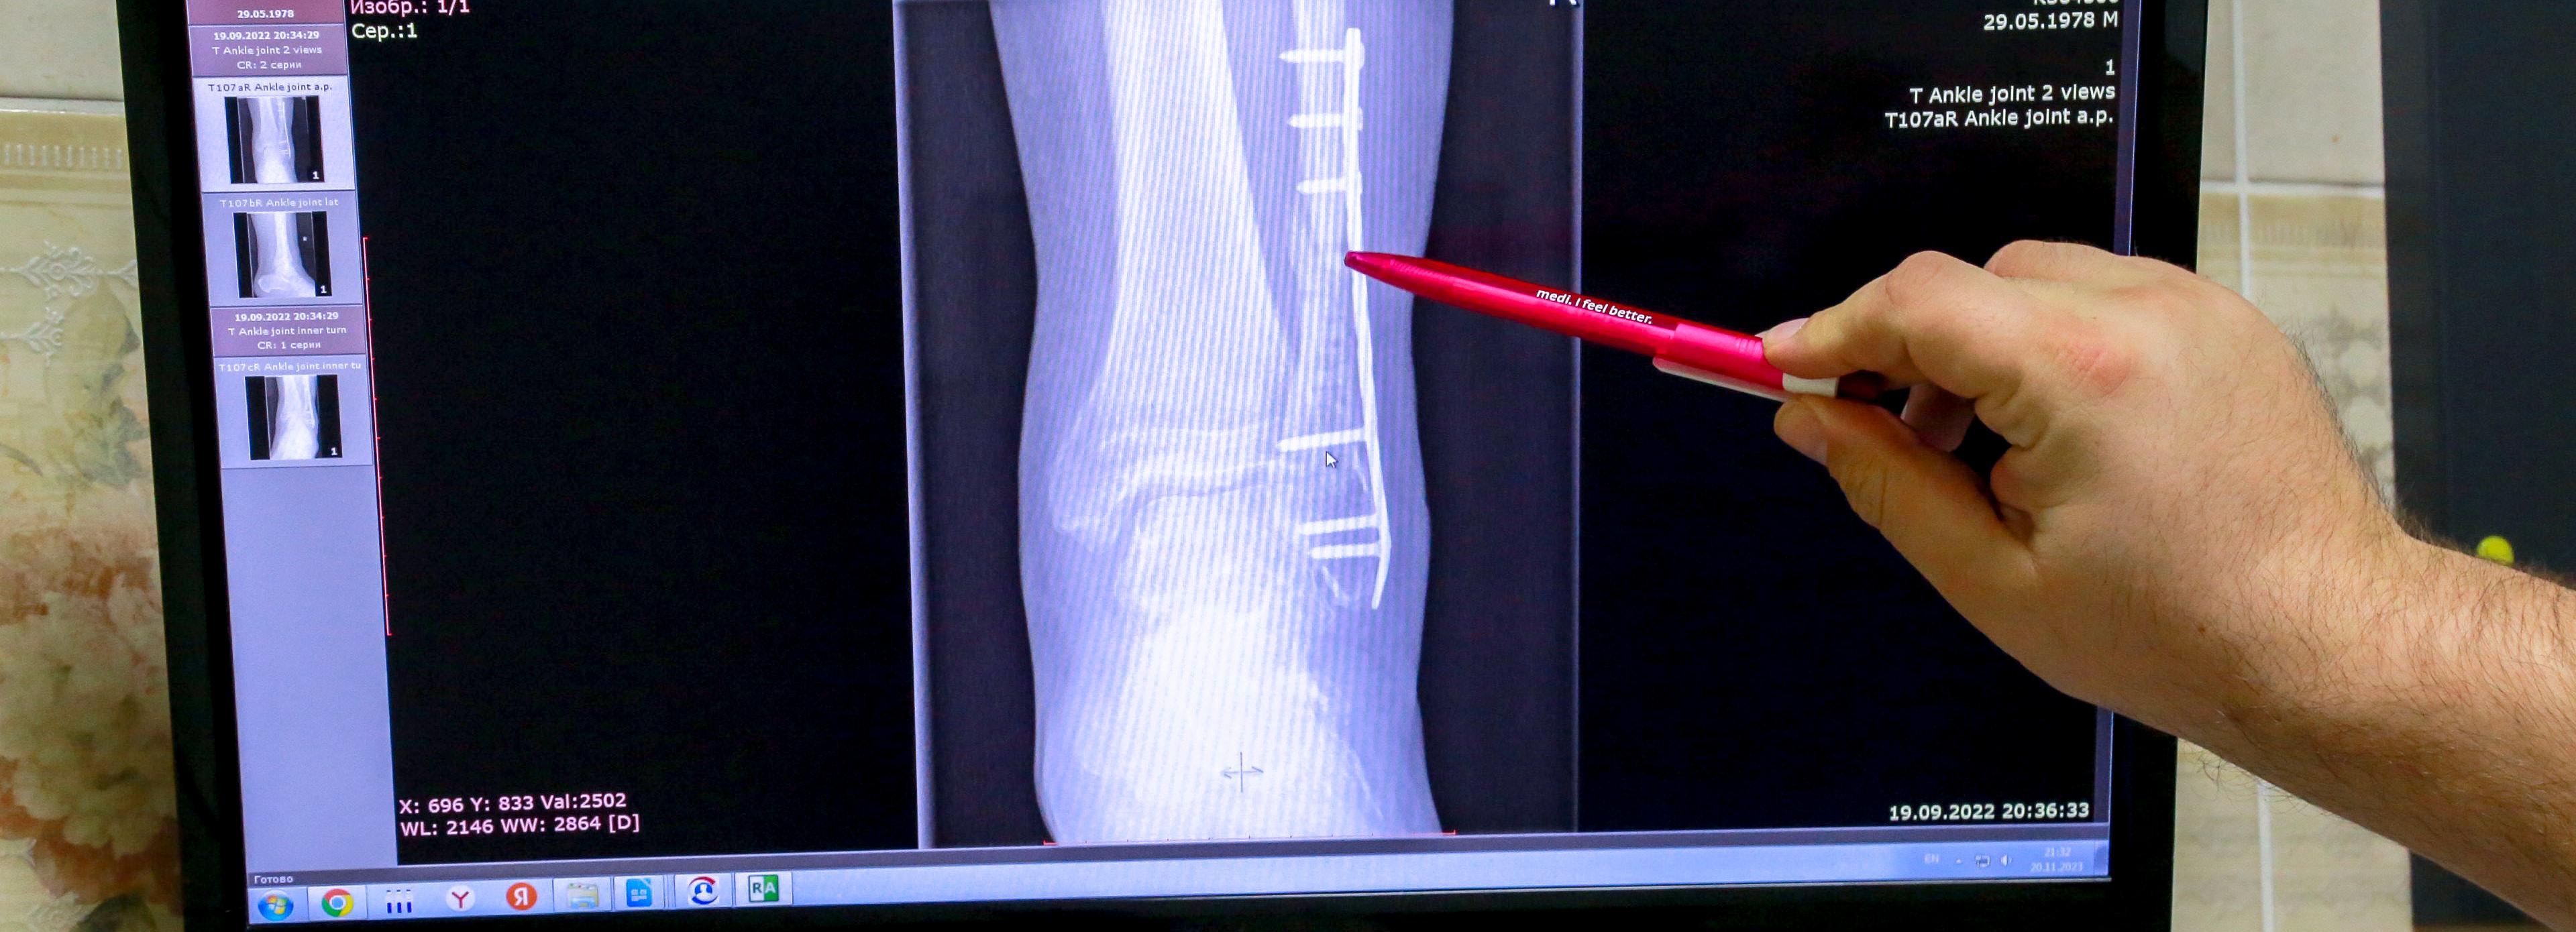

«В рамках программы развития здравоохранения, в рамках программы модернизации первичного звена мы практически завершили переоснащение, замену аналоговых рентгеновских установок на цифровые. Это значительно увеличивает качество тех исследований, которые мы проводим. Плюс если это база медицинского стационарного учреждения, то в некоторых есть компьютерные томографы, что ещё больше позволяет верифицировать диагноз, в первую очередь это касается связочного аппарата», — отметил министр здравоохранения региона Константин Хальзов.